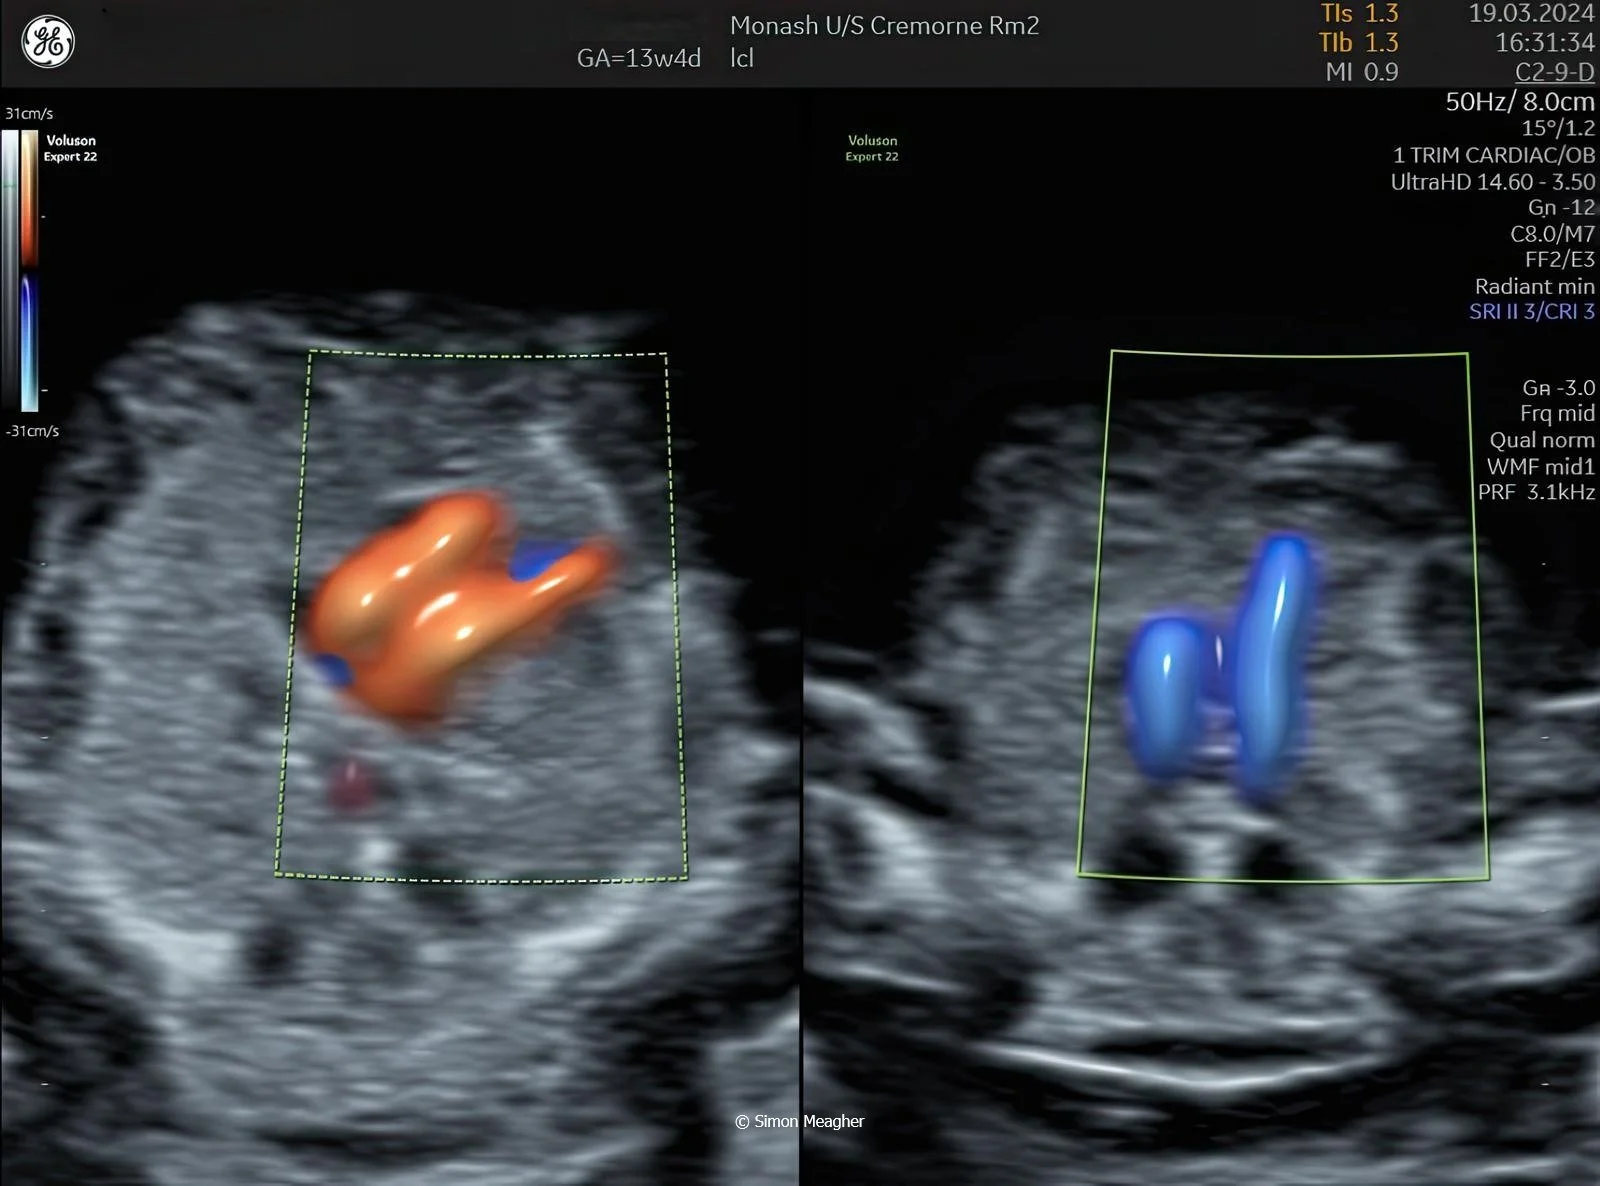

Join Professor Simon Meagher and leading experts for an intensive masterclass designed to transform your clinical practice.

This high-impact, one-day event delivers live scanning demonstrations, real-world case studies, and cutting-edge techniques across all trimesters.